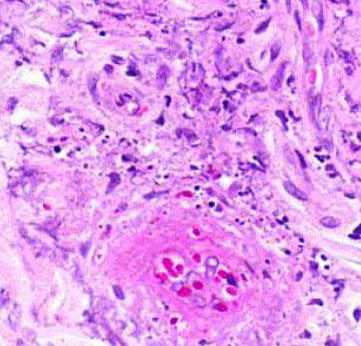

Giant cell arteritis of the breast. The vessel wall has been replaced by granulomatous inflammation. The process has compressed the vessel lumen to near-complete obstruction. A giant cell is shown in this field. B, Giant cell arteritis of the breast. Granulomatous inflammation and fibrinoid necrosis are shown within the wall of this vessel. C, Giant cell arteritis of the breast. The special elastin stain highlights the fragmentation of the internal elastic

lamina in this vessel (hematoxylin-eosin, original magnifications320 [A and B]; original magnification320 [C]).